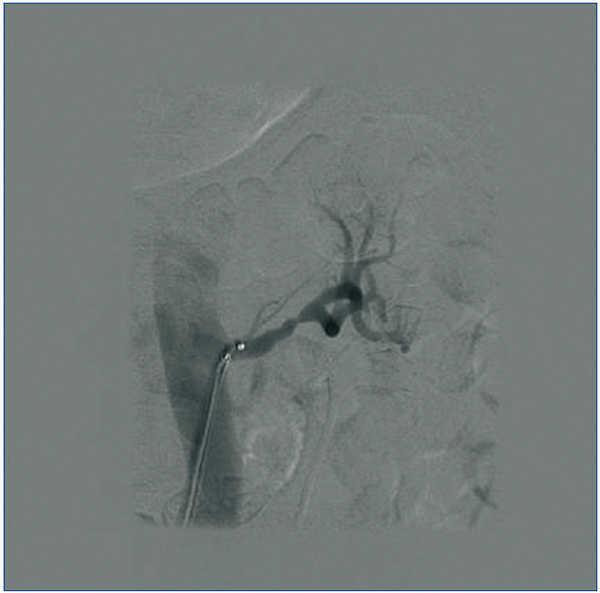

La DNSR se realizó sin complicaciones (figura 2); se decidió no tratar la arteria polar inferior del riñón izquierdo, ya que no alcanzaba el diámetro menor exigido, apreciándose únicamente en el control radiológico inmediato posterior espasmo de la arteria renal izquierda (figura 3), que se solventó con la inyección de nitroglicerina, y por lo que decidimos iniciar antiagregación con triflusal.

Figura 2. DNSR izquierda